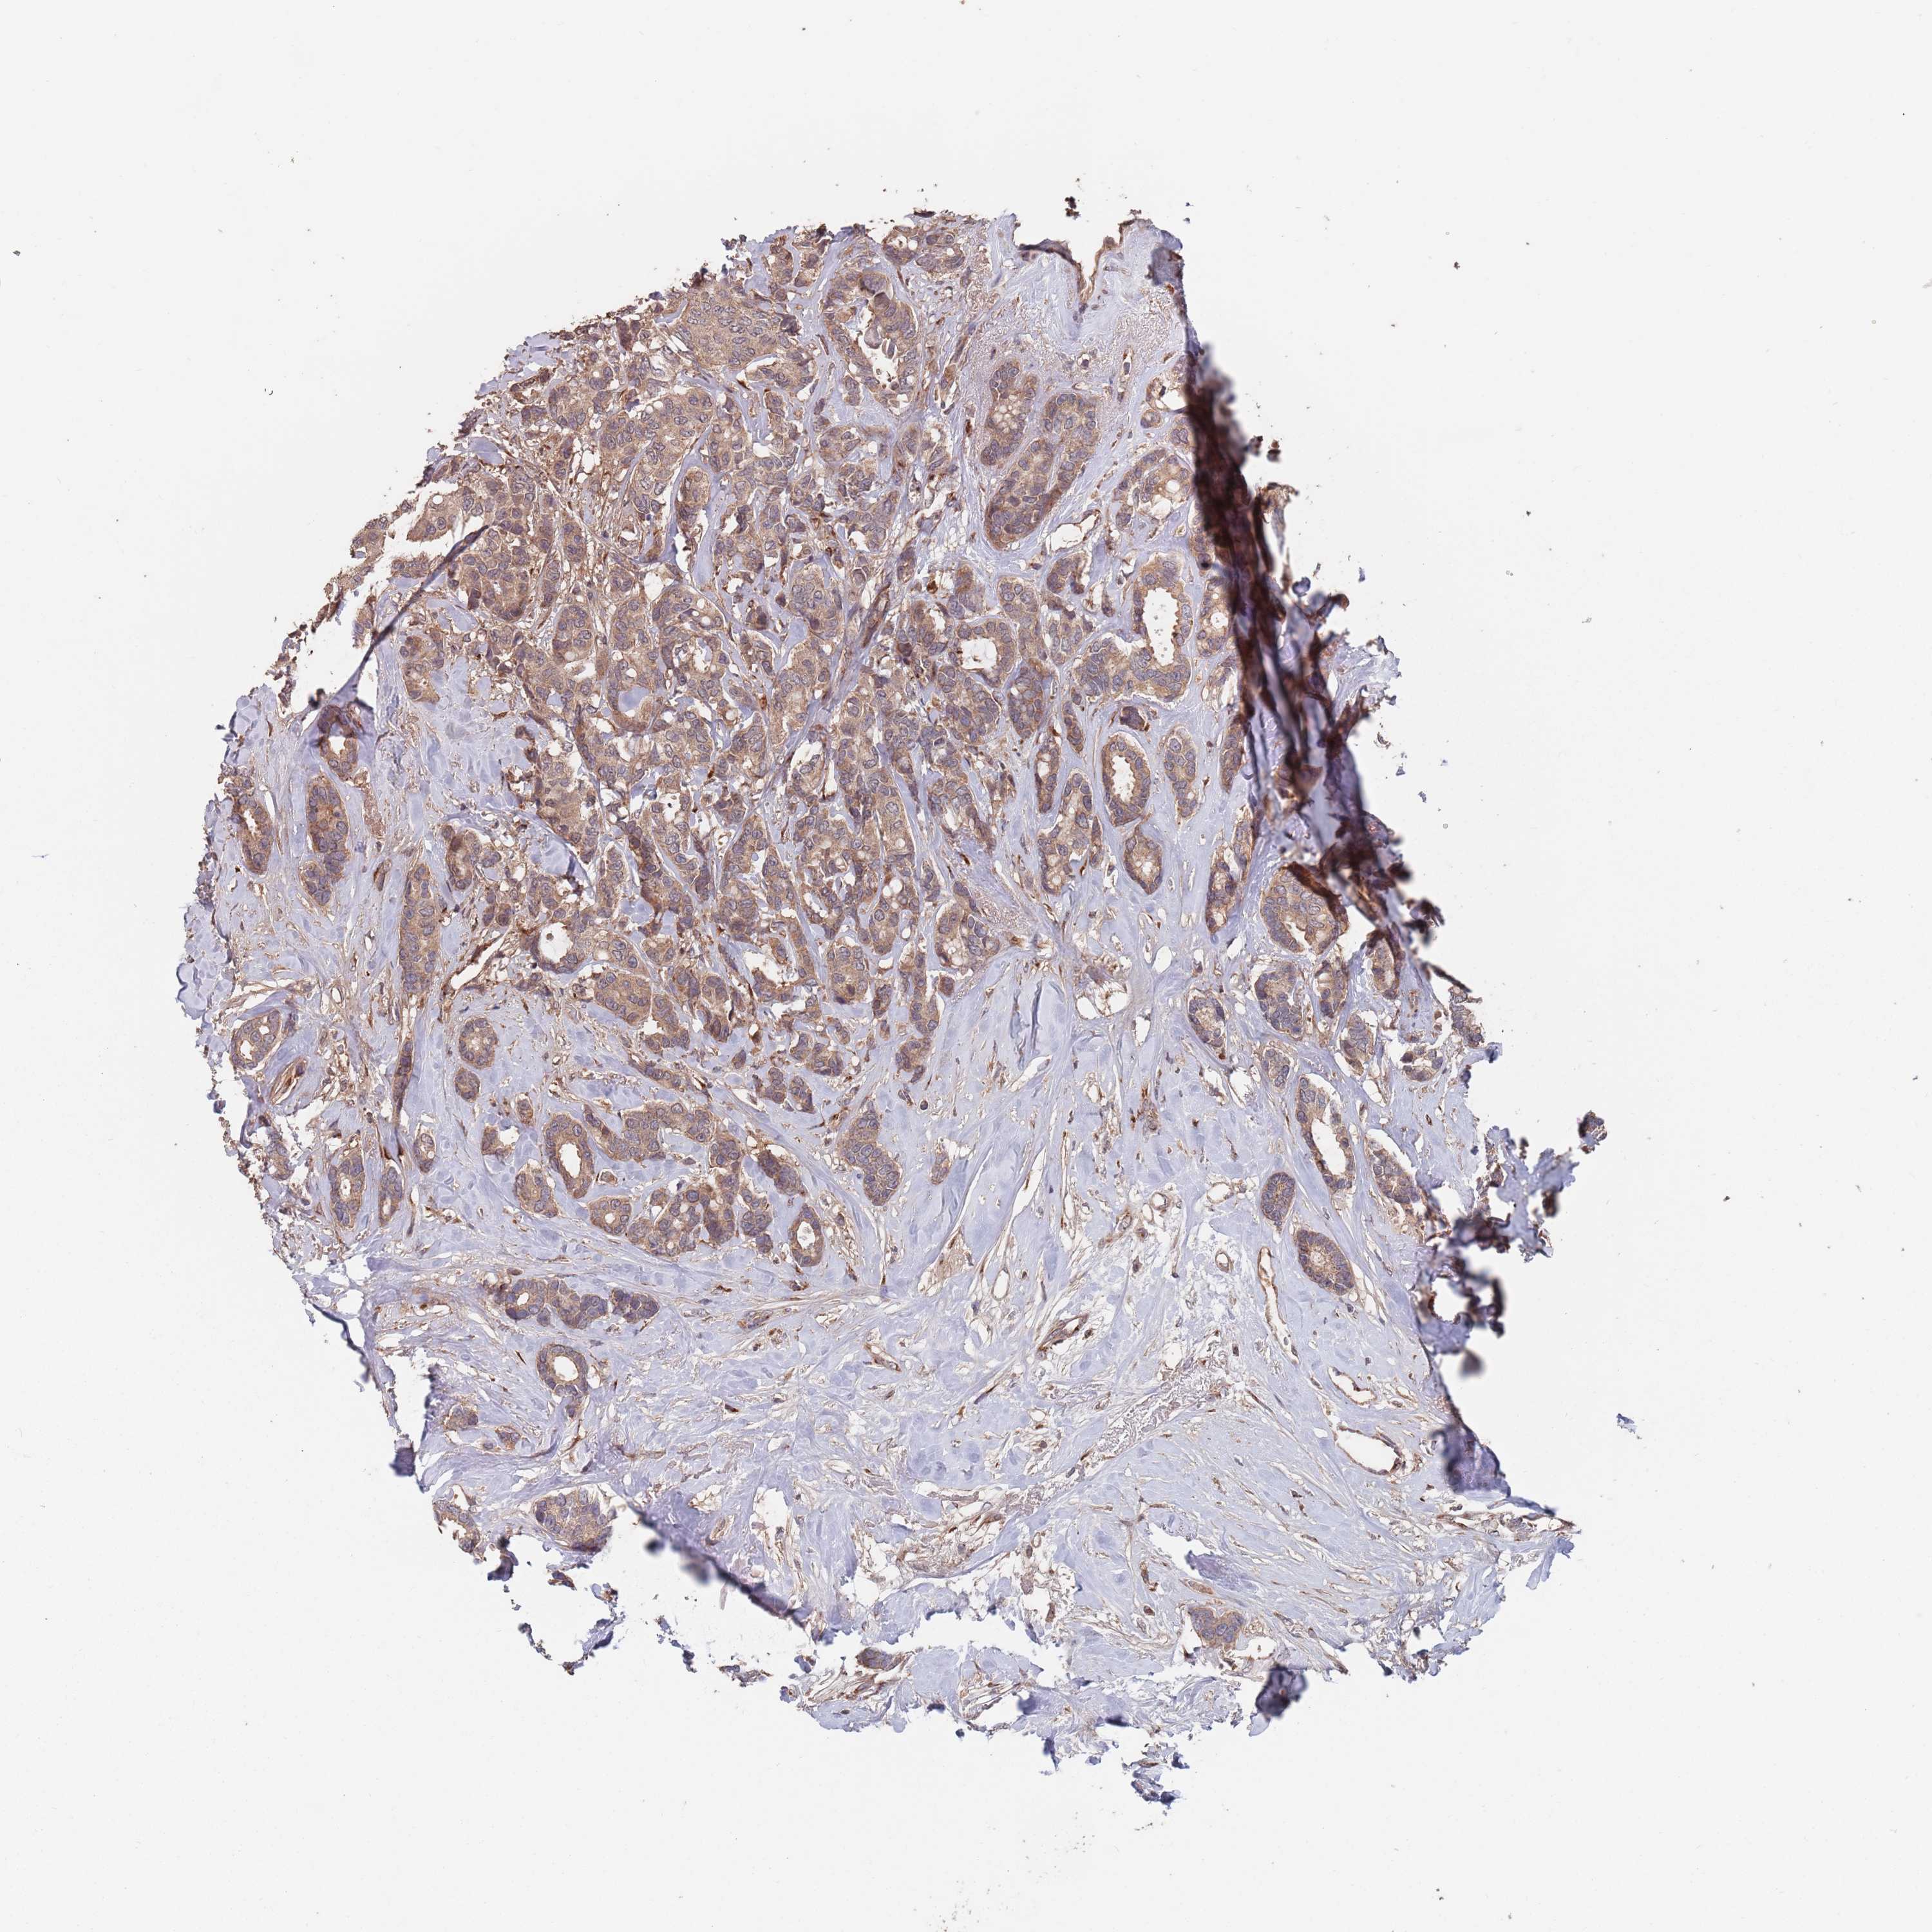

BRCA TCGA BRCA VALIDATION PROTEIN EXPRESSION